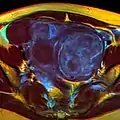

Multiple uterine leiomyoma

Large subserosal fibroid

Multiple uterine leiomyoma with calcification